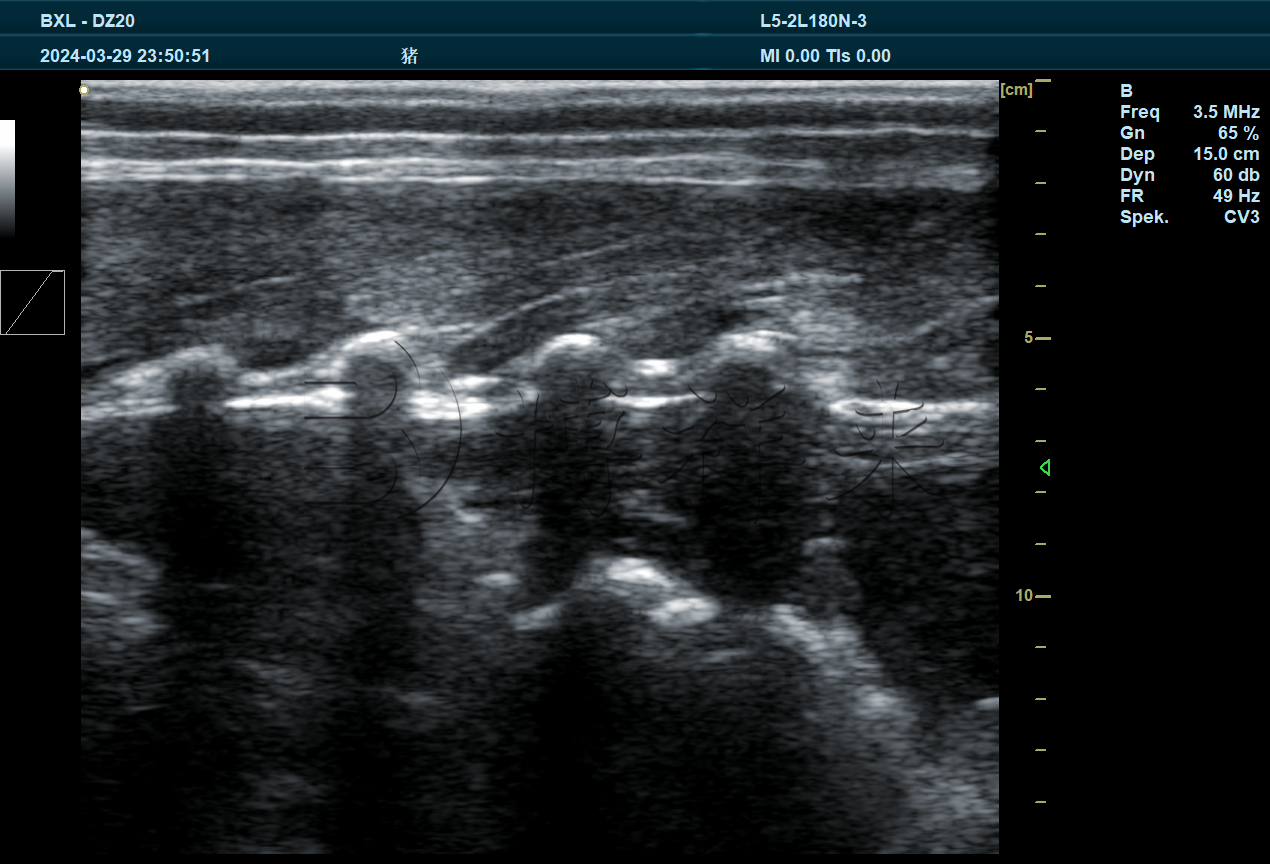

BXL-DZ20是一款多功能兽用全数字彩色多普勒B超仪,可以适配多种探头进行不同超声检测,包括猪牛羊妊娠检测,胎儿发育情况,卵泡黄体发育情况,死活胎,多胎检测,马肌腱韧带检测,背膘眼肌检测等。

4.1、BXL3.5L15A,16cm背膘眼肌专用探头

实拍图片

图像特点